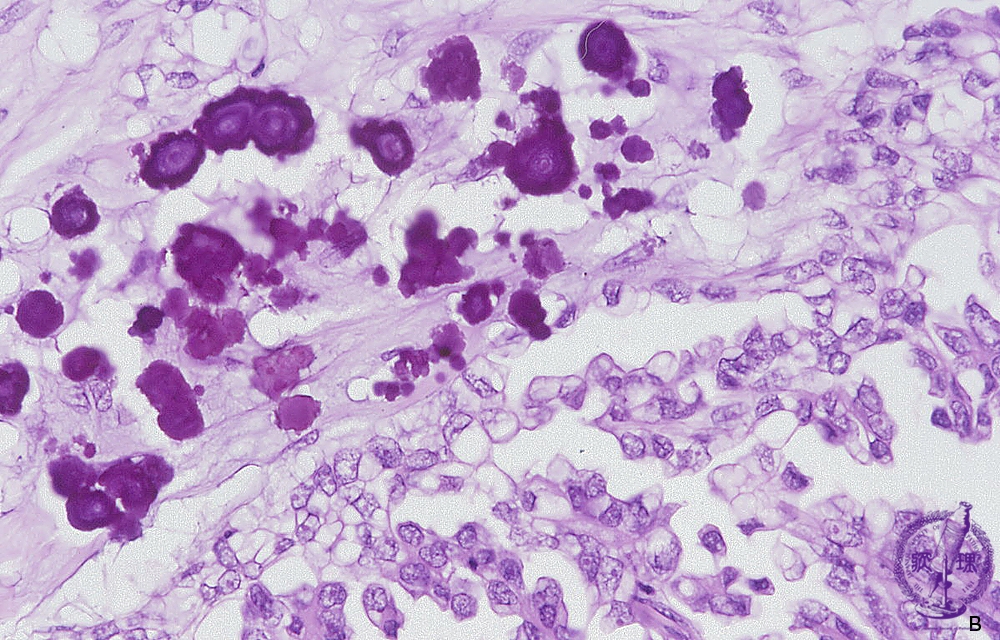

Histology (HE stain, high power): Serous cystadenocarcinoma of the ovary. Calcium deposition called psammoma body can sometimes be identified.

Click the image to see the enlarged image.